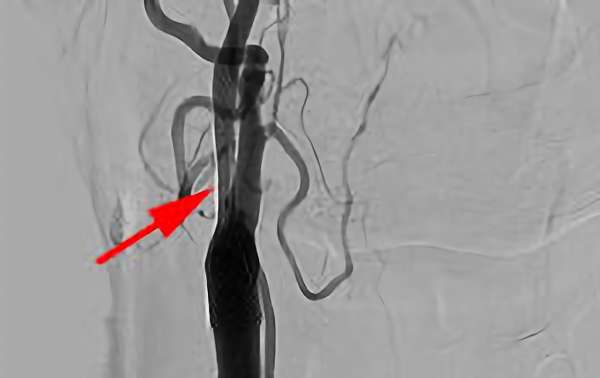

752

'20年2月4日

右内頚動脈狭窄症

80代

大阪府の病院